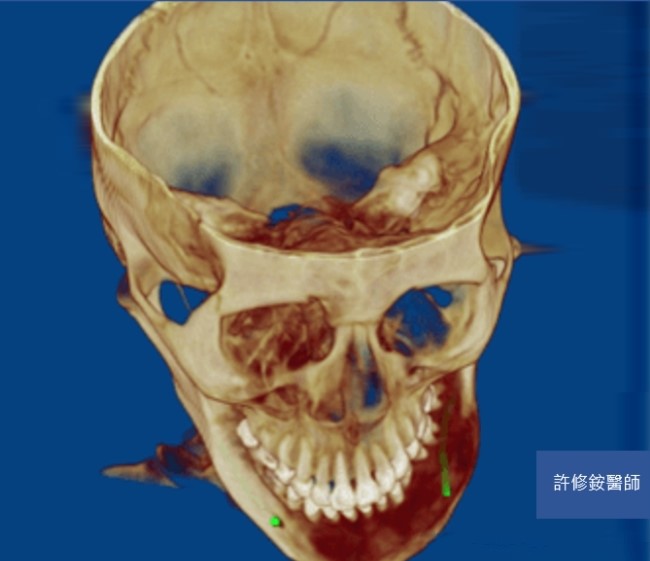

削骨手術需要精密的診斷與計算,加上顏面骨骼有特殊的圓弧與角度,精確的影像是基本要求。3D影像可協助醫師能檢視不同的切面,且影像重組後,專科醫師可自由旋轉影像由各種不同的角度檢視骨骼的變異,除了能完整地檢視病人的顏面骨並精準的訂定治療計劃;客人也能在手術前,藉由3D影像的模擬更理解醫師的解釋內容。

正顎、削骨手術需要精密的診斷與計算,加上顏面骨骼有特殊的圓弧與角度,精確的影像是基本要求。感謝科技進步,3D影像使醫師能檢視不同的切面,且影像重組後,醫師可自由旋轉影像由各種不同的角度檢視骨骼的變異。因此,醫師能完整地檢視病人的顏面骨並精準的訂定治療計劃。病人也能藉由3D影像的模擬更理解醫師的解釋內容。

(黃)過度發育之下顎骨角 (黑線)過度平緩下顎下緣

(紅)下顎骨理想角度120度 (黃)下顎平面角想角度30度

骨頭的切除量依據每個人的需求而有不同。但原則是重新塑造理想的下顎骨角角度以符合美觀(約呈120度),且重新建立下顎平面角(約呈30度),改善下臉部過短的視覺效果。